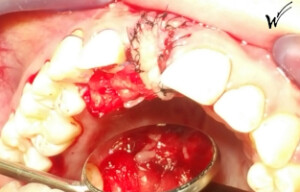

Lors de l’extraction, une greffe épithélio-conjonctive était nécessaire pour restaurer à la fois la hauteur du festonnage gingival et, bien sûr, les papilles gingivales qui disparaissent avec la dent extraite. J’ai choisi d’opter pour une greffe pédiculée avec un prélèvement au palais rétro-incisif.

L’utilisation de membranes de PRF (Plasma Riche en Fibrine) contenant des facteurs de croissance plaquettaires cicatriciels, ainsi que d’injections de PRP (Plasma Riche en Plaquettes), lors de l’intervention, renforce la capacité de reconstruction des tissus mentionnés précédemment. Ces protocoles modernes, constamment perfectionnés par les cliniciens, présentent des avantages majeurs pour la restauration immédiate de la microvascularisation, un élément déterminant pour une cicatrisation optimale à long terme des tissus mous et durs.

L’implant a été positionné dans l’alvéole, aligné avec la racine. À ce stade, un guide chirurgical peut s’avérer extrêmement utile, en particulier pour éviter d’éventuels obstacles anatomiques, tels que des paquets vasculo-nerveux situés dans le trou rétro-incisif.